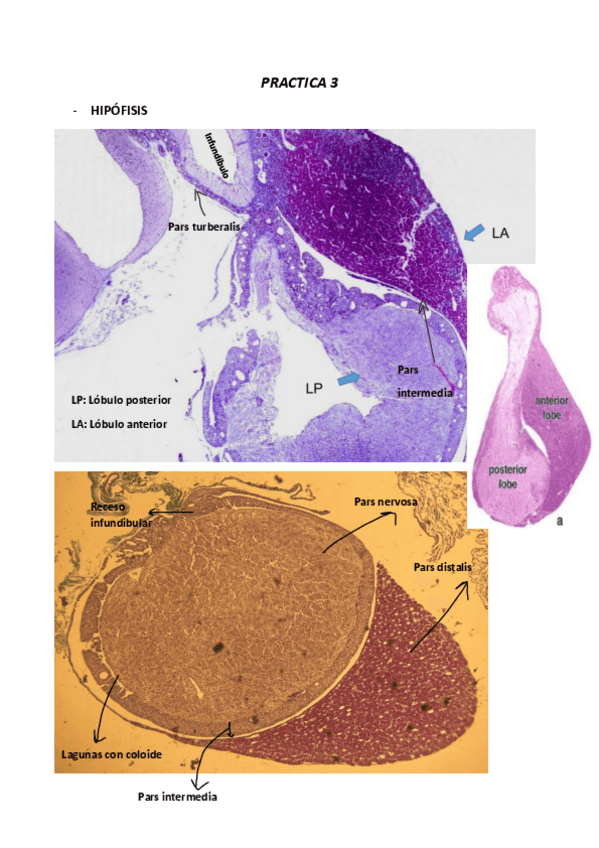

PRACTICAS HISTOLOGIA

PRACTICA-3.pdf